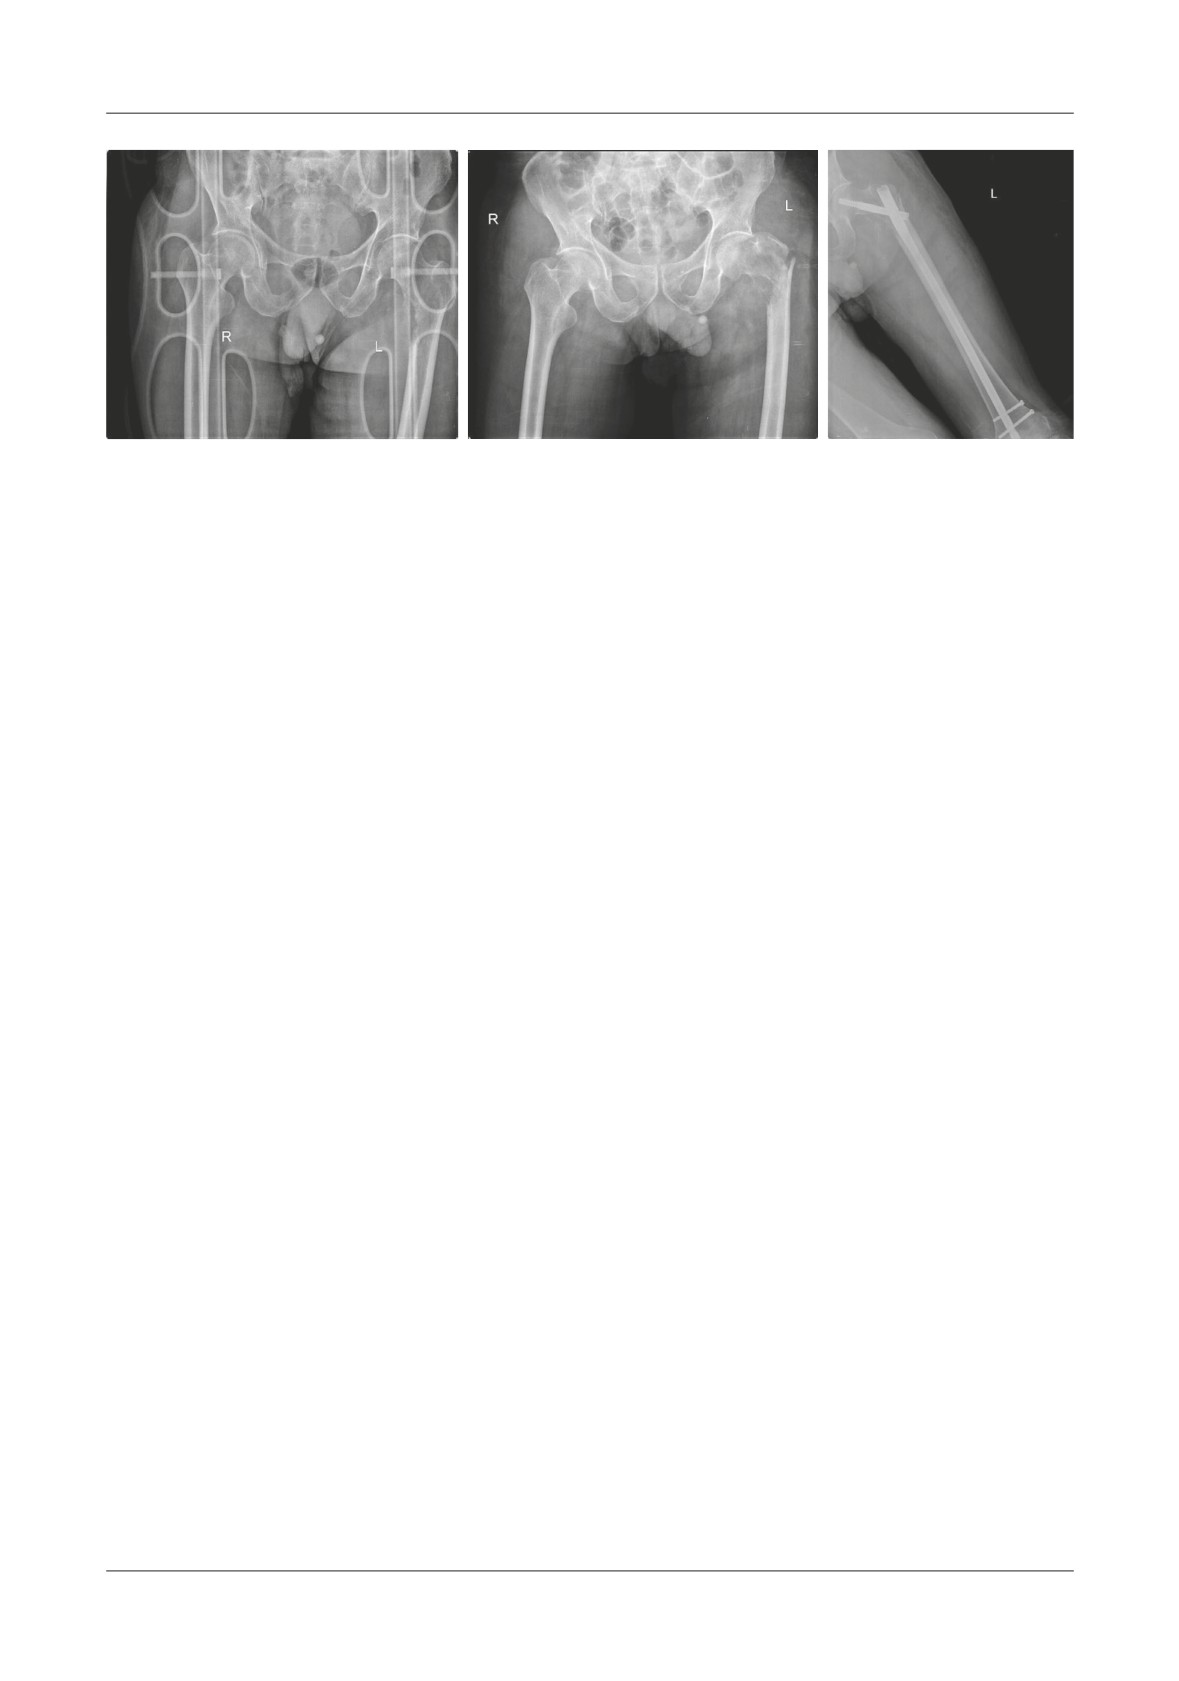

Figure 1. A. Anteroposterior pelvic X-ray of our patient where we can notice the sub trochanteric fracture and the lack of bone

density in that certain area. B. Intra operatory picture taken after the revision prosthesis has been placed.

C. Picture of the tumor mass that has been removed. Te only thing missing is the femoral head.